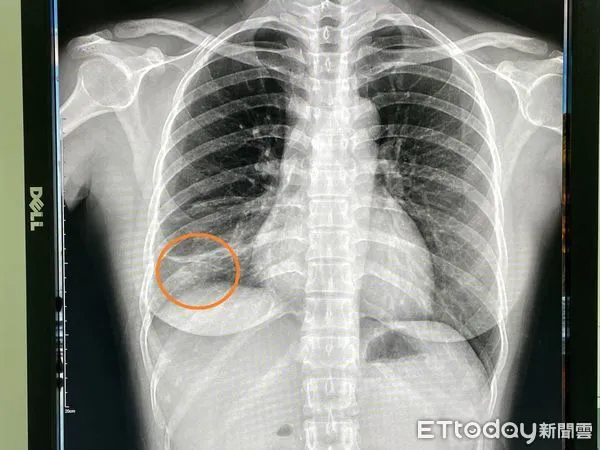

▲傳播力不輸Omicron!女作業員肺結核連咳2個月,醫驚「下肺葉塌陷了」。(圖/院方提供)

近日台灣新冠肺炎Omicron呈現急速擴大流行的趨勢,引發民眾的高度關注,然而另一種傳染性疾病也悄悄散播中。烏日林新醫院胸腔內科主治醫師許人文近日在門診發現一名32歲女作業員,已經咳嗽兩三個月不見好轉,來門診進行胸部X光檢查,發現右下肺葉有一小片扁平塌陷和浸潤的病灶,醫師竟然發現作業員痰液中佈滿了密密麻麻的肺結核菌,屬於罕見的「右下肺葉」開放性肺結核病人,醫院已進行法定傳染病通報。

根據國外文獻統計,下肺葉肺結核的病人,大多以40歲以下的年輕女性為主,肺結核的X光表現,大部分都是在兩側的上肺葉,然而在「下肺葉」的個案非常少見,常常只有零星個案被報導,也因此常常會被醫療人員所忽略,再加上肺結核具有「非立即性傳染、不易診斷」之特性,醫師初步需要先排除肺炎、肺膿瘍、或是肺癌,再進一步考慮是否為肺結核的可能性!